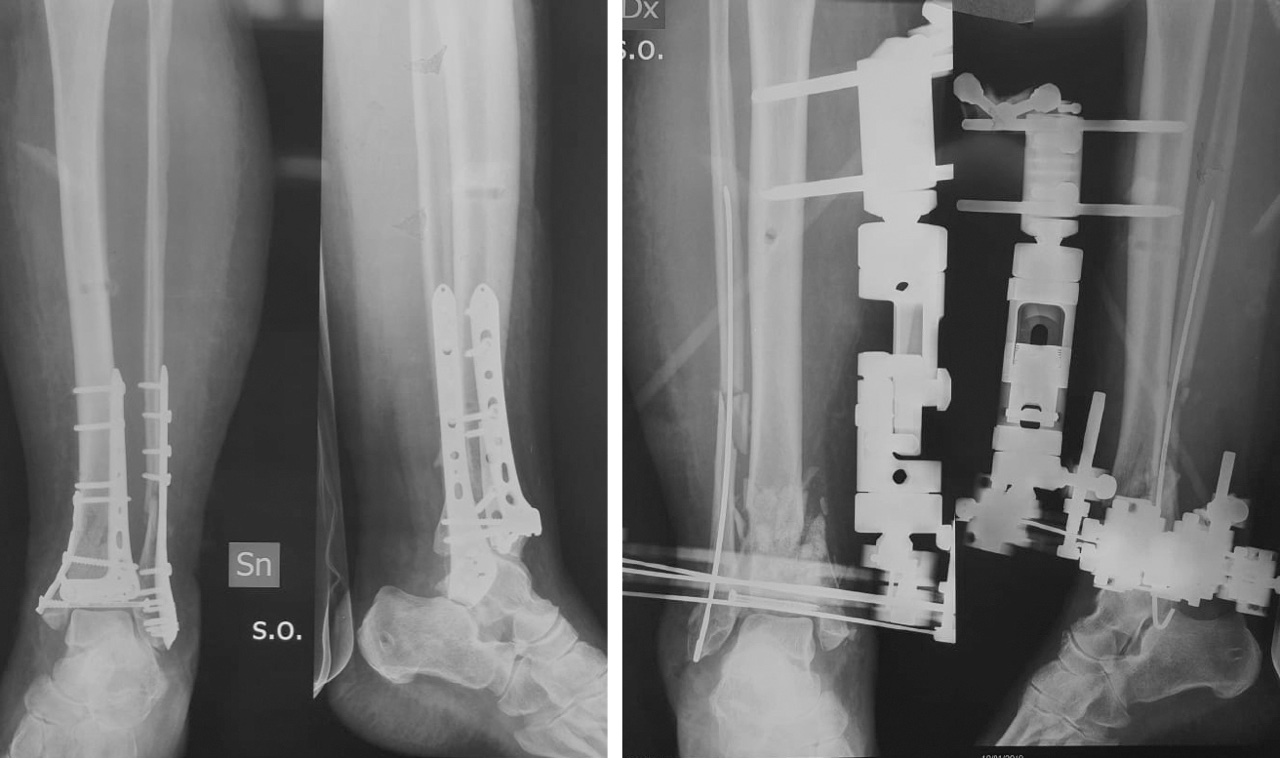

Il trattamento delle fratture di pilone tibiale deve essere accuratamente pianificato, le vie di accesso sono molteplici, il posizionamento del paziente può variare e la scelta dei mezzi di sintesi è particolarmente vasta. Per poter garantire il miglior trattamento al paziente è imprescindibile un accurato studio radiografico della frattura. La diagnosi può essere definita grazie alle classiche radiografie eseguite nelle tre proiezioni (AP, LL e AP obliqua) (Fig. 1).

). Questo esame di primo livello consente la classificazione della frattura secondo il sistema proposto da Ruedi e Allgower in tre stadi a seconda del numero dei frammenti e della scomposizione. Il sistema alfanumerico proposto dall’AO invece, classifica le fratture di pilone tibiale come 43B e 43C, cioè le fratture di tibia (4) distale (3) parzialmente (B) o completamente (C) articolari. La diagnosi eseguita tramite radiografia ci permette di passare alla prima fase del trattamento, cioè il posizionamento di un fissatore esterno temporaneo in distrazione associato o meno alla sintesi definitiva del perone. Una volta eseguita questa prima fase il paziente può essere sottoposto all’imaging di secondo livello con TC secondo il protocollo “Span & Scan”. La distrazione della tibiotarsica attraverso il fissatore esterno ci permette infatti, grazie a un meccanismo di ligamentotassi, un parziale riallineamento dei frammenti di frattura e di conseguenza un esame più accurato. Nel 2013 Cole et al hanno pubblicato un lavoro in cui, studiando nel dettaglio le scansioni assiali delle TC di 38 fratture di pilone tibiale, hanno potuto dimostrare la presenza di pattern più o meno comuni a tutti i pazienti 4. Il 100% delle fratture infatti aveva una rima che coinvolgeva la superficie articolare tibio-peroneale e da questa si dipartivano due linee di frattura (creando un pattern a Y) verso le porzioni anteriori e posteriori del malleolo mediale (Fig. 2).

La prima fase consiste ancora nella stabilizzazione temporanea (Fig. 3).

Il protocollo proposto da Sirkin e Sanders prevedeva la sintesi definitiva del perone da effettuare in acuto e la stabilizzazione temporanea con fissatore esterno temporaneo assiale posizionato per via mediale. Nel corso degli anni la fissazione temporanea con fissatore monoassiale è stata via via abbandonata a favore del costrutto a delta che garantiva una stabilità maggiore. Anche la riduzione e sintesi in acuto della frattura di perone è e stata rivisitata nel tempo, la scelta degli autori fu viziata dalla scarsa disponibilità delle vie d’accesso e dalla limitata conoscenza dei pattern di frattura (Fig. 4).